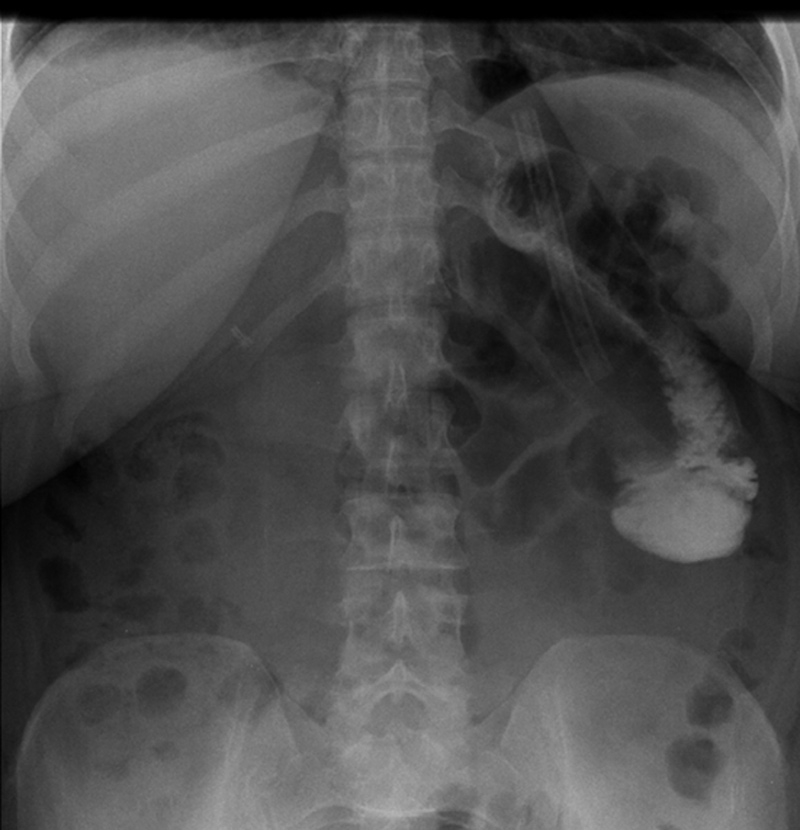

Figure 2

X-ray showing a stenosis at the level of the jejunojejunal anastomosis.

In two patients, the results showed a stoma obstruction due to a postoperative edema at the level of the GJ anastomosis (1.2%) (fig. 1). The post gastric bypass diet was delayed and the UGI was performed again at postoperative day 4 with resolution of the edema. One patient presented an anastomotic stenosis at the level of the JJ anastomosis with delayed emptying (0.6%) (fig. 2). The patient was treated conservatively with success as well. Of note, the patients who presented an abnormal UGI study were all symptomatic with early nausea and vomiting.